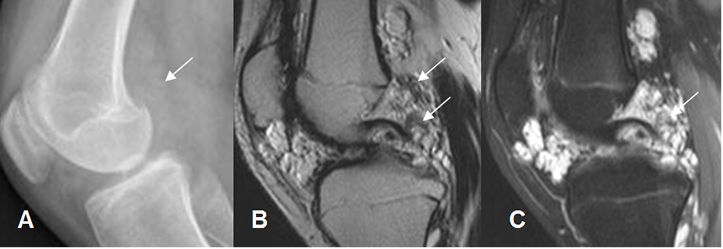

Fig 193. Condromatosis sinovial.

A: Rx oblicua. No se encuentran anormalidades.

B: RM sagital en FFE y C: RM coronal en STIR. Moderado derrame articular, con cuerpo

libre no calcificado en el espacio suprapatelar.

Fig 194. Condromatosis sinovial.

A: Rx lateral. Imágenes densas proyectadas sobre la región intercondílea.

B: RM sagital en T1 y C: RM sagital en STIR. Lesión hipointensa en ambas secuencias,

por detrás del LCP, que corresponde a cuerpo libre calcificado.